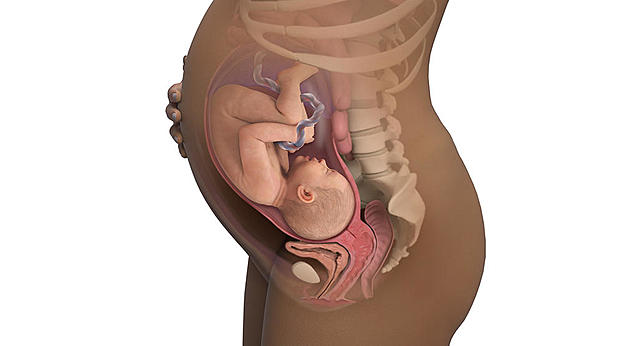

Desarrollo del feto en la semana 36: Ya pesa dos kilos y medio

Su rostro es liso y a medida que ha ido guardando grasa, la mayoría de las arrugas ha desparecido en la semana 36 de embarazo.

Los pulmones son los únicos órganos que aún siguen madurando.

Sus huesos se han endurecido, excepto los de la cabeza que son más blandos y flexibles para poder atravesar el canal del parto.

Sus movimientos son fuertes y vigorosos y es fácil adivinar un pie o el codo en forma de protuberancias, y si los presionas ligeramente comprobarás que se revuelve.